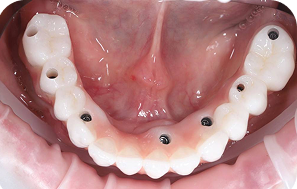

Для комплексного лікування повної адентії (відсутності зубів) використовують метод All-on-4 – вживлення 4 імплантів, на які фіксується незнімна конструкція, яка замінює всю щелепу в деяких випадках використовують ще додатково два імплантати для кращої стабільності подальшої конструкції і тоді така методика називається All-on-6-вживлення 6 імплантатів.

Це технологія яка дозволяє закріпити повній зубний ряд зубів всього на 4 або на 6 імплантатах аледуже часто з вікористанням титанової “шинуючої” фрезированої балки , і чим меньша кількість встановлених імплантатів при тотальнії реабілітації, тім вирогідність шинування імплантатів за рахунок балки вище. тому ця методика має свої плюси та мінуси та свої покази та протипокази.